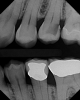

A 32 year-old female patientpresented with old composite restorations in tooth Nos. 18 and 19 that exhibited marginal leakage with potential for recurrent decay (Figure 10).  After excavation, both teeth had deep decay beyond the extent of the restorative material, with tooth No. 19 having a "pinpoint" carious exposure of the pulp chamber (Figure 11).  Figure 12 is a diagrammatic representation of the therapeutics that were used after removal of infected dentin and control of the bleeding from the pulp exposure.  A pulp protectant/liner that is indicated for use on a direct pulp exposure (TheraCal LC, Bisco Dental Products) was placed directly on the exposed area and light cured.  Both preparations were then filled with a bioactive dentin replacement (TheraBase, Bisco Dental Products) to a point just apical to the dentoenamel junction (Figure 13).  Selective etch protocol was then used, etching the enamel (Select Etch HV, Bisco Dental Products) for 15 seconds (Figure 14), then rinsing with water and drying.  Next, a universal bonding agent (All-Bond Universal, Bisco Dental Products) was placed, air thinned, and light cured (Figure 15).  Figure 16 is an occlusal view of the completed restorations.  Both teeth are planned to be followed and radiographed periodically to ensure that the pulps are responding favorably.

Fig 10. A preoperative occlusal view of tooth Nos. 18 and 19 with composite restorations that are exhibiting marginal breakdown.

Figure 10

Fig 11. After removal of the existing restorations and associated recurrent decay, both cavities are very deep and there is a pinpoint pulpal exposure on tooth No. 19.

Figure 11